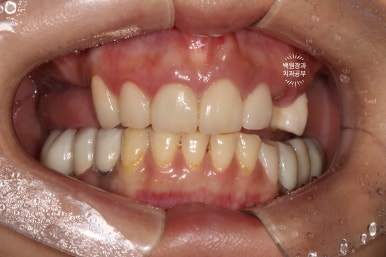

앞니 지르코니아 브릿지와 왼쪽 어금니 임플란트 완성!

앞니 지르코니아 브릿지와 왼쪽 어금니 임플란트가 완성되었습니다.

너무 색깔도 깔끔하게 잘 나오고... 만족스러운데요, 어디가 무엇인지 아시겠어요?

파란색으로 표시된 3개짜리가 앞니 지르코니아 브릿지이고,

보라색으로 표시된 2개짜리가 어금니 임플란트입니다.

진짜.. 내 치아라고 해도 잘 모르실거에요.

양 옆모습을 돌려서 보시면 위어금니와 아래어금니가 확연히 비교되는 것을 보실 수 있을겁니다.

일단 치아 경계 잇몸에 은색으로 보이는 부분 없이 깔끔하게 마무리가 되었습니다.

색상도 무조건 하얗지만은 않아서 개인적으로 더 자연스러워졌다고 봅니다.